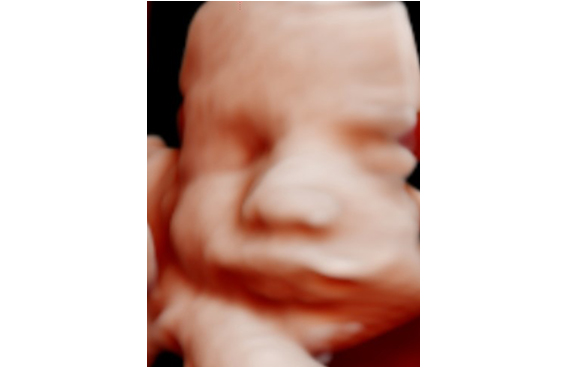

Es la manera de ver a tu bebé en tres dimensiones a tiempo real y en movimiento. Podrás conocerlo antes de nacer y ver sus gestos.

Se puede realizar en cualquier momento de la gestación aunque preferimos realizarla a partir de la semana 28 porque por la madurez fetal realiza más gestos como sacar la lengua, reír, bostezar , etc y además con la incorporación de la Inteligencia Artificial a la ecografía 5D esta se convierte en una imagen hiperrealista , es como será tu bebé cuando nazca.